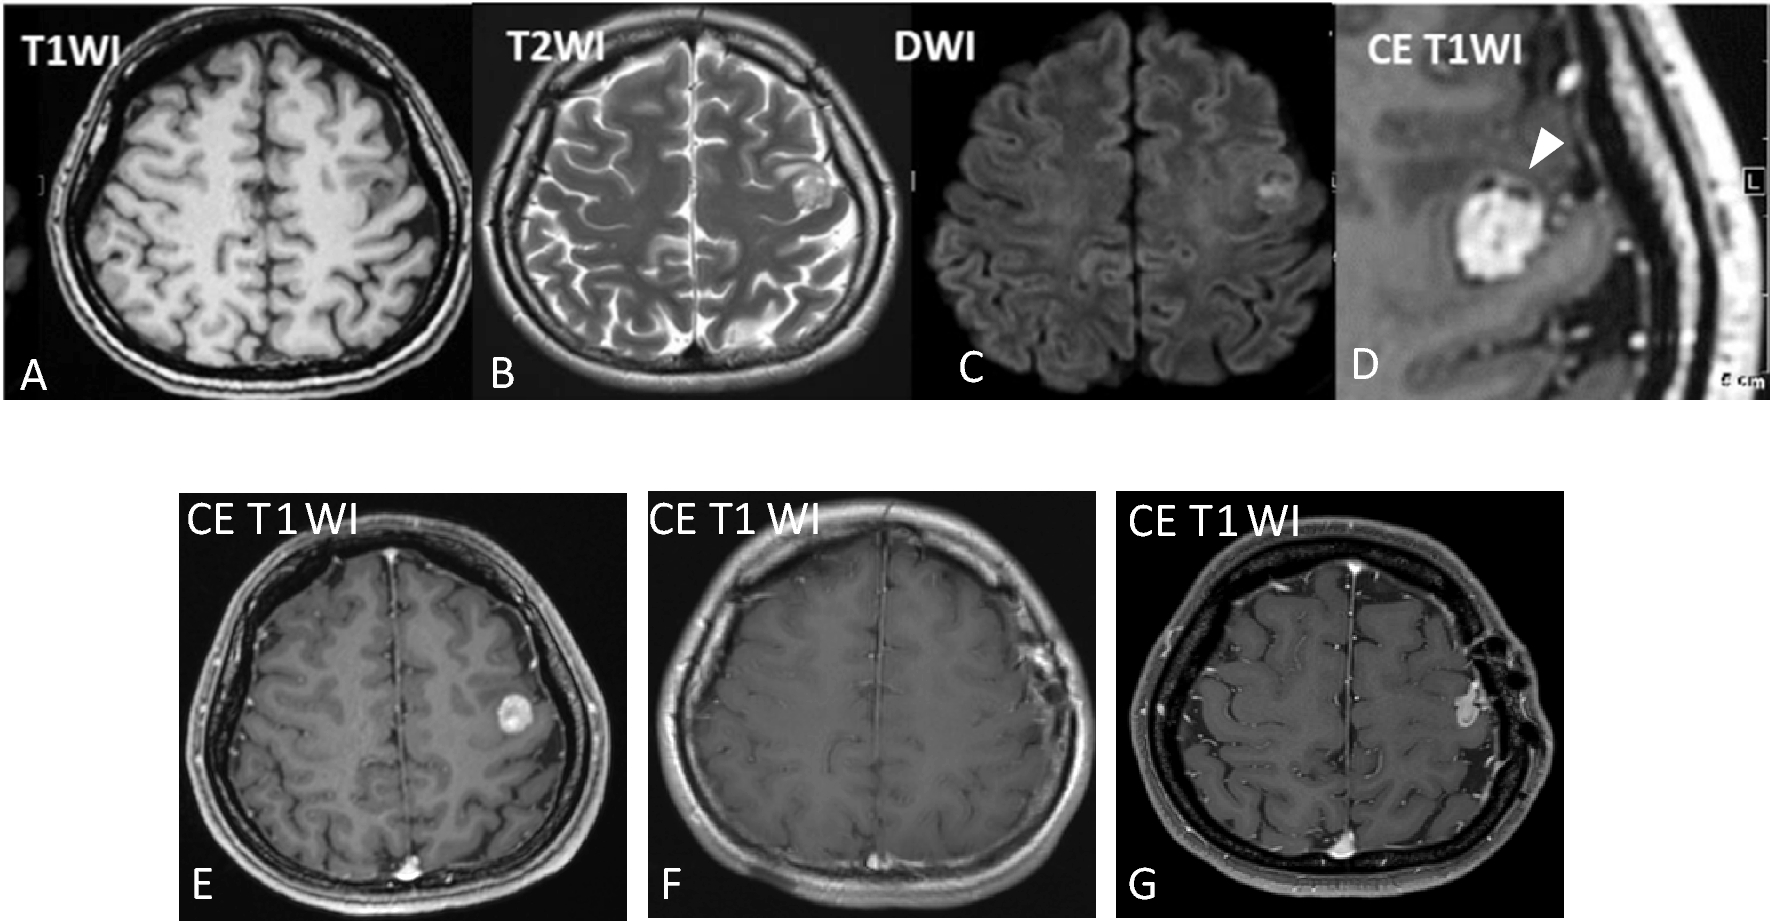

Chen Y, Tian T, Guo X et al (2020) Polymorphous low-grade neuroepithelial tumor of the young: case report and review focus on the radiological features and genetic alterations. BMC Neurol 20:123